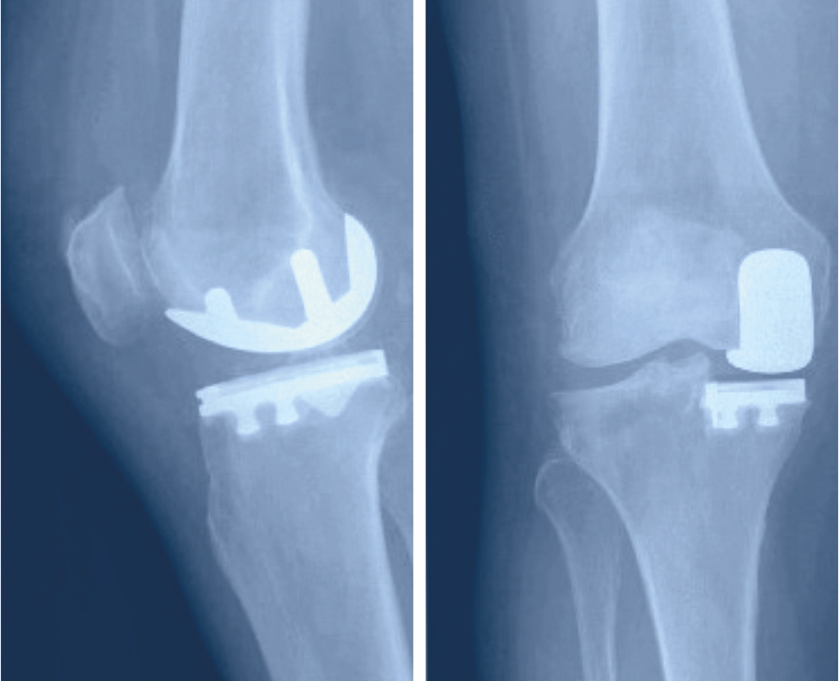

Dieser wird zwischen die Metallteile gesetzt, um die ideale Führung des Gelenks zu gewährleisten und zu verhindern, dass die Metalloberflächen sich aneinander reiben. Je nach Ausweitung der Arthrose besteht heute die Möglichkeit, nicht immer das ganze Knie zu ersetzten sondern gezielt Teilprothesen zu verwenden. Dies hat den Vorteil, dass nur der beschädigte Gelenkanteil ersetzt werden muss.

Die beschädigten Oberflächen des Gelenks werden unter Zuhilfenahme von Schnittschablonen abgetragen, damit das Ersatzgelenk passgenau eingebracht werden kann. Zur genauen Platzierung der Schnittschablonen werden konventionelle Metallinstrumente verwendet, es können aber auch personifizierte Instrumente oder eine Computernavigation zum Einsatz kommen. Durch die Schnittsetzung und die Implantation der Prothese werden grosse Abweichungen der Beinachsen korrigiert, leichte O- oder X-Beine, die der Patient allenfalls schon immer hatte, werden aber belassen.

Der Zugang erfolgt über einen Hautschnitt vorn über der Kniescheibe. Damit eine gute Sicht aufs Gelenk möglich wird, wird es auf einer Seite der Kniescheibe eröffnet. Zur Fixierung der Prothesenteile am Knochen wird meist Knochenzement verwendet.